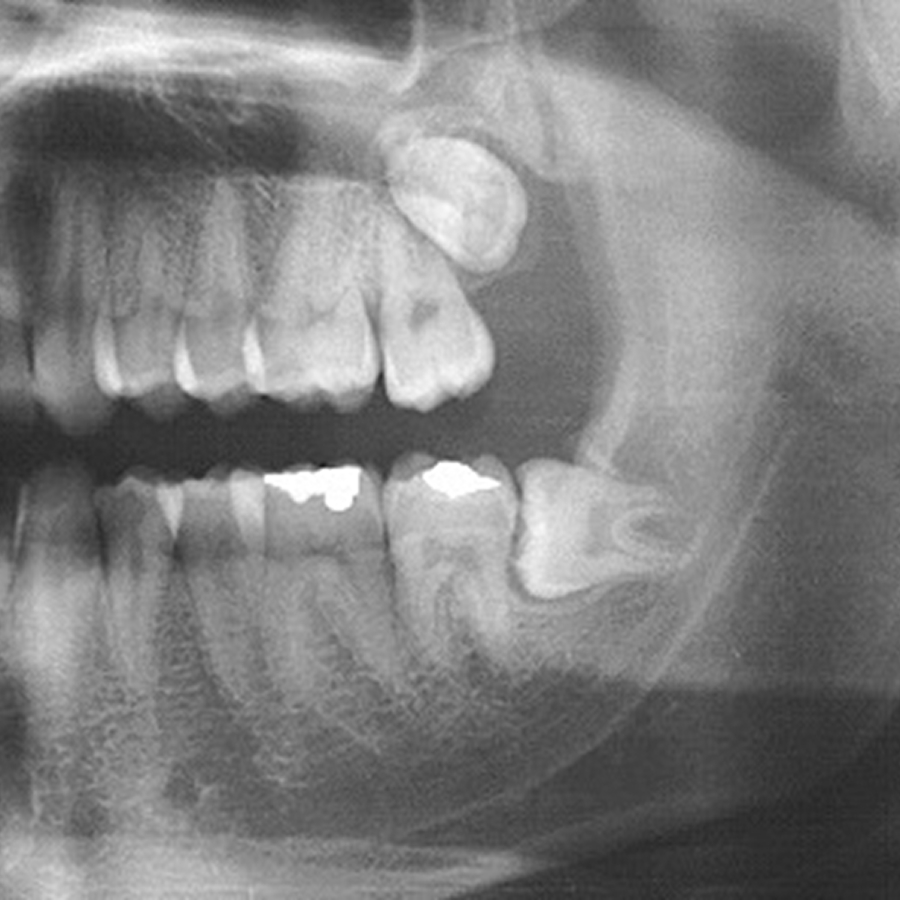

• dentes que nascem tortos ou empurrando outros dentes;

• sisos inclusos, que ficam presos no osso ou parcialmente erupcionados e podem assumir diferentes posições.

No último caso (sisos inclusos), uma das posições assumidas é o siso deitado, quando o dente fica horizontalizado e aumenta o risco de comprometer os dentes vizinhos. Assim, a remoção do siso deitado é a conduta mais segura.